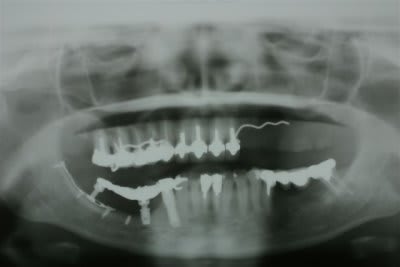

1 Radiographie panoramique avant implantation.

Les deux implants du haut ont été perdus.

2La greffe autologue prélevée à la hanche à totalement fondu.

Il ne reste que la vis d'ostéosynthèse qui avait servi à fixer le greffon.

3 Radiographie Panoramique de la correction